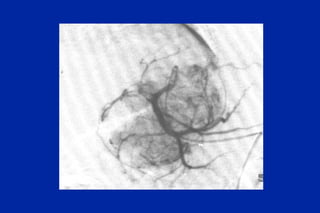

Este documento resume los principales tipos y técnicas de angiografía. Describe brevemente la angiografía, arteriografía, flebografía y linfografía, así como las técnicas de contraste y materiales utilizados. También explica los principales accesos vasculares, la técnica de Seldinger, la angiografía por sustracción digital y algunas técnicas endovasculares comunes.